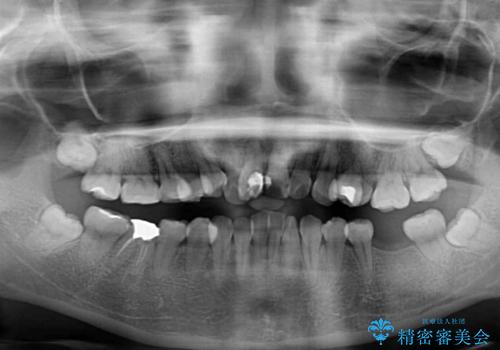

- 放置した虫歯や抜いたままの奥歯、前歯のデコボコを気にして来院された患者様です。

口元の突出感は少なく、下顎の叢生は軽微なものであったので、叢生の強い上顎左右の小臼歯を1本ずつ抜歯し、ワイヤー装置にて矯正治療を行うこととしました。

矯正治療を行う前に、根管治療の必要な上顎前歯と下顎大臼歯の根管治療を行い、矯正治療の途中で下顎の欠損部にインプラント埋入することとし、矯正治療後に補綴治療を行うこととしました。